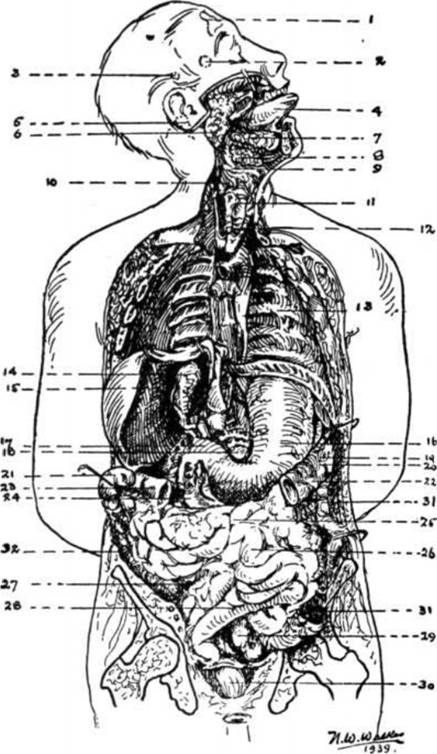

It is my opinion that the most important subject missing in elementary schools, is ANATOMY. This sketch is included here to serve as a guide and handy reference. The numbers indicate the location of the various parts.

1. The Frontal Sinus, in the forehead, above the eye where mucus accumulates eventually when we eat excessive amounts of concentrated starches, and drink too much milk.

2. The Pituitary Gland (or Body) is located directly behind and just a little below the level of the bridge of the nose.

3. The Pineal Gland, located in the mid-brain, back, and slightly higher than the Pituitary.

4. The Tongue, one of the most mischievous organs of the human body.

5. The Medulla Oblongata, the central Nerve-telephone-exchange, is situated in the lower middle part of the head between the upper lip and the base of the skull, just above the Atlas or first cervical vertebra.

6. The Parotid Gland, which becomes swollen and causes Mumps, especially when children and adolescents indulge in excesses of starches and candies.

7. The Sub-Lingual Gland.

8. Sub-Maxillary Gland.

9. The Epiglottis.

10. The Pharynx

11. TheThyroid Gland, one of the most vital and important glands of the body. It requires Iodine-foods for proper functioning. When improperly nourished causes Goiter.

12. The Larynx.

13. The Spleen is located towards the back of number 19. Back of the Ribs at this point are the Lungs; back of the Lungs, the Stomach the Splenic Flexure of the Colon, the Spleen, the tip of the Pancreas and the left Kidney.

14. The Gall Bladder - That most essential, though greatly abused gland. The Liver (No. 15) has been raised in this picture, with a hook, to show its location. Its duct leads into the Duodenum (No. 24) to lubricate the intestines with the bile. To remove a Gall Bladder (instead of cleansing the system naturally) deprives the unlucky individual of Natures means for lubricating the intestines sufficiently.

15. The Liver -The most marvelous laboratory in Creation. Created by Nature to withstand on an average about 40 to 50 years of abuse after birth before perceptible and usually uncomfortable disintegration begins.

16. The Stomach - That organ which controls the Individual, unless the Individual learns to control it.

17. The Pyloric Valve, between the Stomach and Duodenum.

18. The Pancreas, the gland which enables the body to utilize natural sugars (such as are found in raw fruits and vegetables) and which breaks down when refined sugars and starches are used to excess causing diabetes.

19. The Splenic Flexure of the Colon, or the bend in the Colon leading from the Transverse Colon (No. 22 and No. 23) to the Descending Colon (No. 31).

20. The general location (further back) of the Kidneys.

21. The Hepatic Flexure of the Colon, leading from the Ascending Colon (No. 32) to the Transverse Colon (Nos. 23-22).

22. The Transverse Colon, frequently becomes a gas storage balloon when 23 . tense nerves or impactions of waste matter in the Flexures (Nos. 21-29) prevent the gas from expanding and being expelled. Asa result of improper nourishment this section of the Colon easily loses its tone and then sags, causing what is more picturesquely described as a prolapsus.

24. The Duodenum, or Second Stomach, where the alkaline digestive processes we so frequently interfered with by the presence of acid or acid-forming foods with concentrated starches and sugars, often resulting in ulcerous conditions which individuals enjoy calling their Duodenal Ulcers.

25. The area of the Solar Plexus.

26. The Small Intestines, about 25 feet of perpetual trouble sooner or later, for these who insist on eating what they want when they want it.

27. The Appendix, that marvelous safety gland whose secretion prevents gas forming bacteria and other noxious germs from passing into the Small Intestines from the Colon. It has of late been allowed to function more normally since the education of the laity in the use of frequent enemas and skillful colonic irrigations.

28. The Bladder is in this region.

29. The Sigmoid Flexure of the Colon leading from the Descending Colon (No. 31) to the Rectum (No. 30).

30. The Rectum, the cesspool of the body, which should be washed out with enemas or colonic irrigations quite often.

31. The Descending Colon.

32. The Ascending Colon.